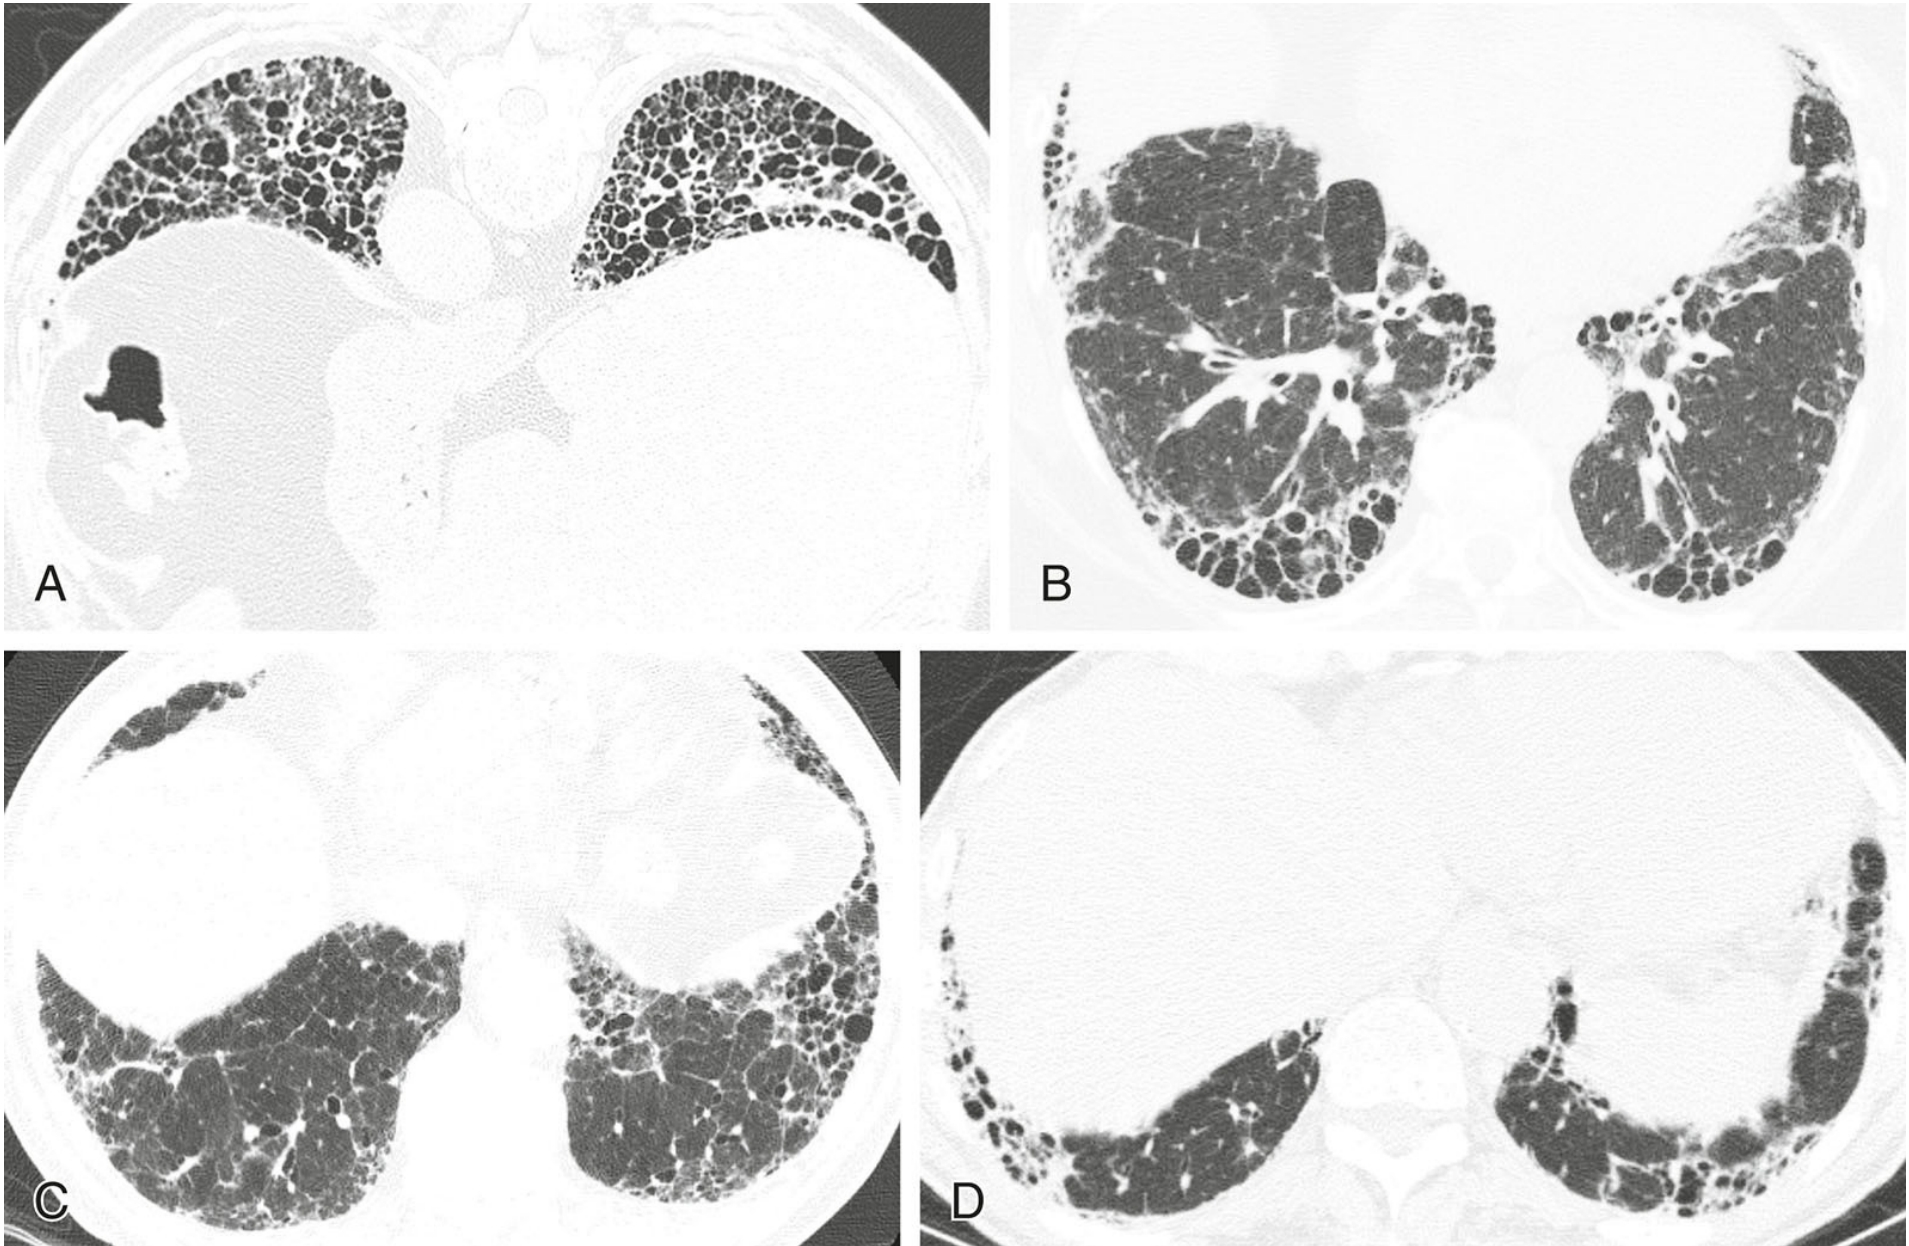

27548bcf9c93bc25a1cd816613e8485a.png

纤维化型非特异性间质性肺炎(NSIP)的典型表现。

4例纤维化型NSIP,每例均显示不规则网状影(蓝箭)和牵拉性支气管扩张(红箭)为主要异常。紧邻胸膜下肺区不受累(A至C)高度提示本病,但有时无此征象(D)。蜂窝征缺如或不明显。